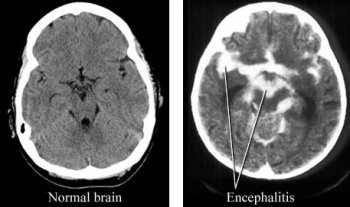

- Томография головного мозга. Если клинические проявления и анамнез предполагают воспаление мозга, назначается компьютерная томография (КТ). Для более детального трехмерного анализа рекомендуется магнитно-резонансная томография (МРТ).

Дифференциальная диагностика проводится для уточнения типа энцефалита, его происхождения (первичный или вторичный), а также для исключения или подтверждения менингита или токсической энцефалопатии.